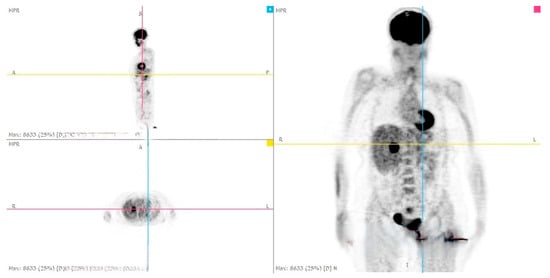

| Our Case Rep | 52 | F | R | 9 × 7 × 6 | None | Laparoscopic Adrenalectomy + Nephrectomy | CT | 12 (alive with liver metastasis) |